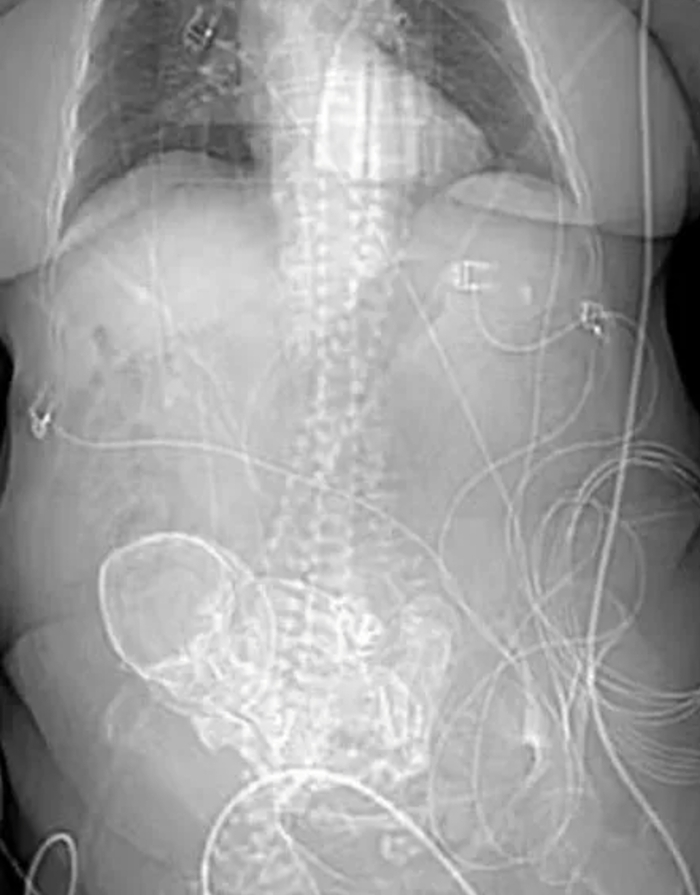

Литопедион переводится с греческого как "каменный ребенок". Это происходит, когда у женщины наступает внематочная беременность, при которой плод умирает, но становится слишком большим, чтобы его можно было реабсорбировать в ее организме. Внематочная беременность - это когда плод растет вне фаллопиевых труб или матки.Каменные дети могут родиться при абдоминальной внематочной беременности, когда плод растет в брюшной полости.Мертвый плод остается там, со временем образуя кальциевую оболочку и затвердевая в рамках естественной реакции иммунной системы. С одной стороны, эта оболочка защищает мать от инфекции, но с другой, остаётся незамеченной десятилетиями.Каменные дети невероятно редки, но могут возникать всего с 14 недель беременности вплоть до 9-ти месячного срока.И хотя количество зарегистрированных случаев невелико, нет ничего необычного в том, что он десятилетиями остается недиагностированным.

В статье 1996 года в журнале Королевского медицинского общества говорилось, что только 290 случаев литопедиона когда-либо были задокументированы медицинской литературой.Сейчас, почти 30 лет спустя, их все еще меньше 300.

С помощью 3D сканирования врачи обнаружили кальцинированный плод, который находился в ее теле 56 лет.

В декабре 2021 года такое же открытие было сделано у 73-летней женщины в Алжире. Рентгеновское сканирование показало, что мертвый плод весом 4,5 кг и на седьмом месяце развития находился там 35 лет.